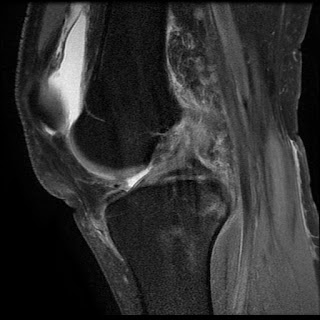

Tibial Tunnel Cyst post ACL Reconstruction

Screw Fractures and Tibial Tunnel Cyst extruded into pretibial area.

MR Imaging of Complications of Anterior Cruciate Ligament Graft Reconstruction